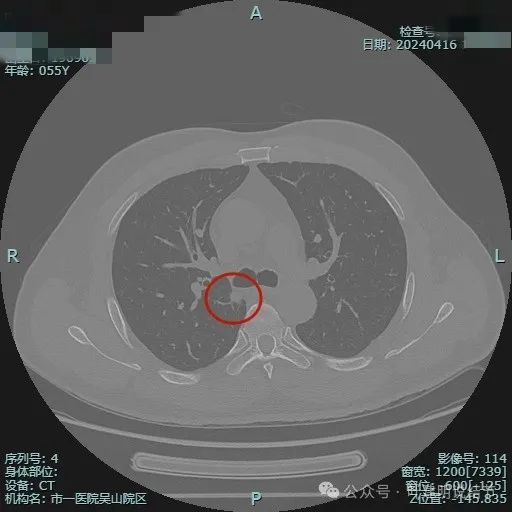

我们先来看2024年4月的病灶影像:

病灶出现,位于右上叶靠近肺门侧,此层显得像磨玻璃密度,轮廓较清。

其实应该实性密度的,前面层面应该是较为边缘部位的关系。病灶表面有点毛糙。

结节毛刺明显,而且是细毛刺。

有微血管走向病灶,结节与纵隔侧紧贴,但胸膜牵拉不明显。

有明显血管征,而且进入的血管是弯曲改变走行的。

表面不平显毛糙,有细毛刺。

此层显得病灶缺乏膨胀性,边缘较为平直。

边缘区较淡,也显得有点散。

病灶没有钙化。

纵隔窗可见。